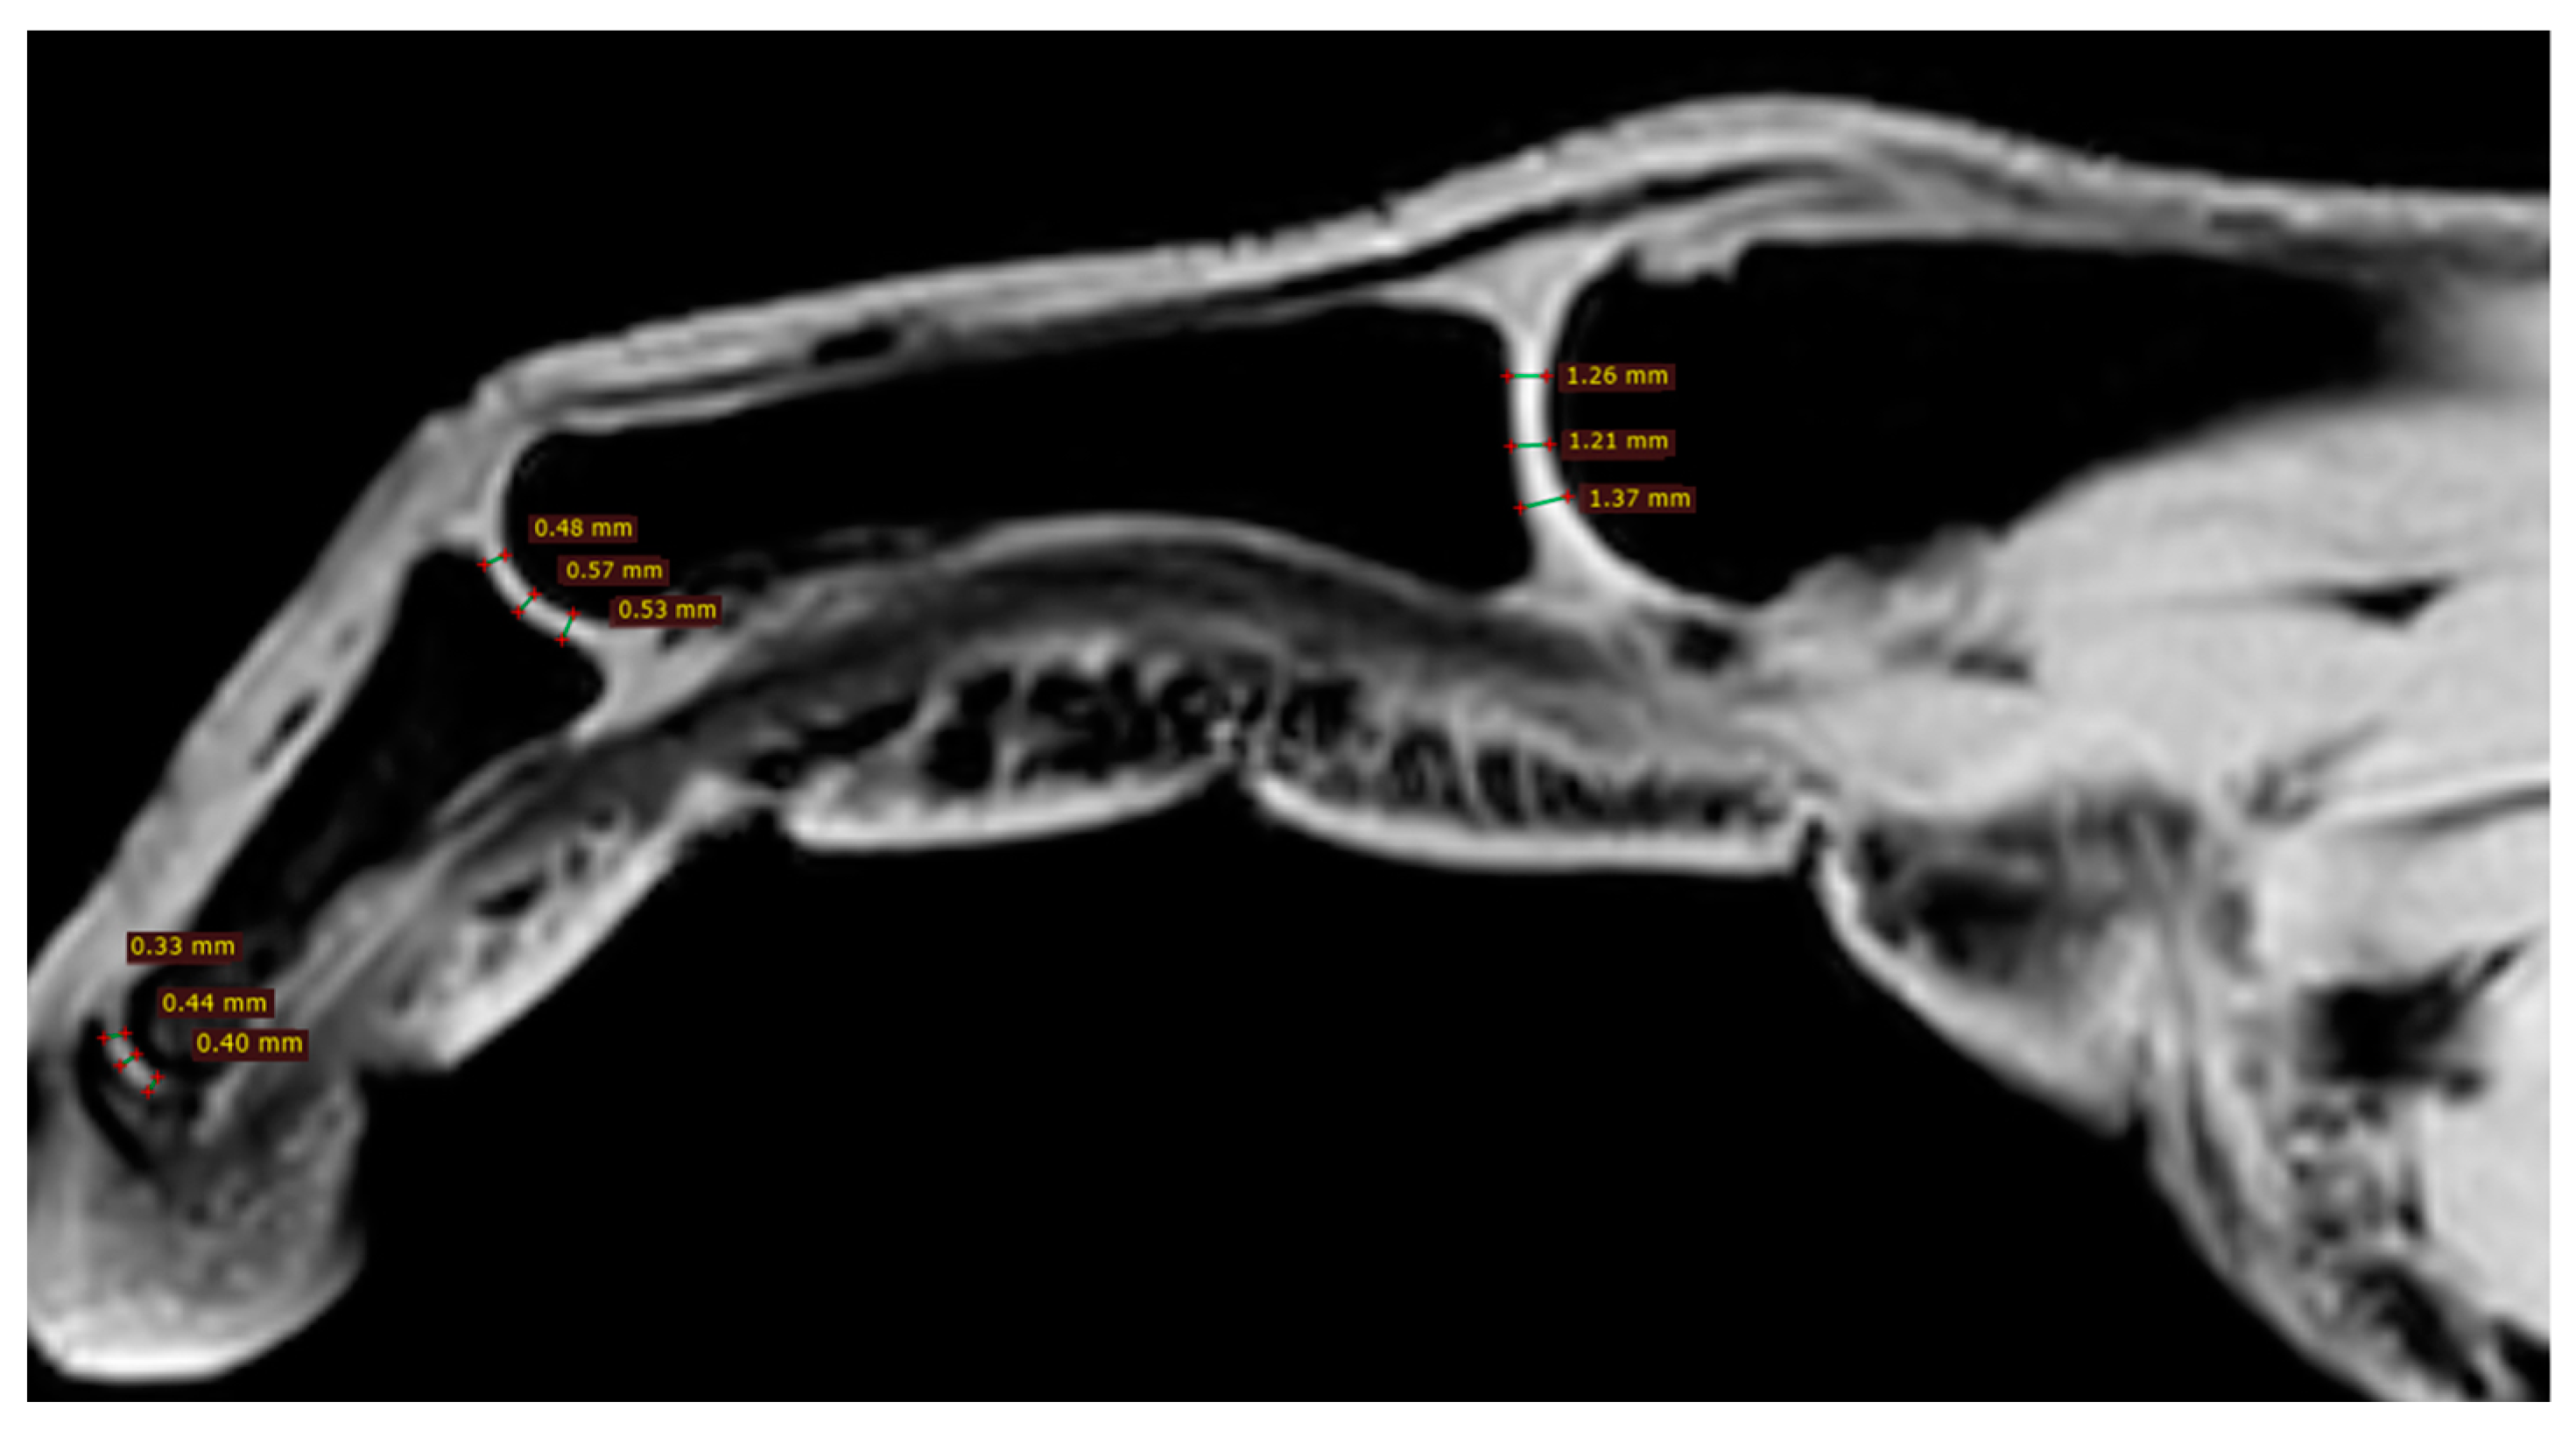

All participants were examined with the three-dimensional quantitative MRI (3D q-MRI). The Philips 3T scanner was used with the coil for small parts. After obtaining structural T1 and T2 scans, the WATS 3D sequence was performed. The WATS sequence is dedicated to the cartilage evaluation and highlights the subchondral cortical layer. Due to the application of a 3D sequence, we were able to obtain the true sagittal cross-section of each finger (Figure 3). This was vital because, in some patients, contractions did not allow for anatomical position of fingers during examination. After adjusting the planes, we measured the distance between two cortical layers for each finger joint in its middle transverse dimension, obtaining three measurements (in volar 1/3, dorsal 1/3, and middle 1/3) and calculating a mean (Figure 4 and Figure 5). The distal phalanx length (DPL), the cartilage thickness of distal interphalangeal joints (DIPJ), proximal interphalangeal joints (PIPJ), interphalangeal joint (IPJ), and metacarpophalangeal joints (MCPJ) in all participants were measured.

Figure 5.

Three measurements of cartilage thickness in each finger joint (in volar 1/3, dorsal 1/3, and middle 1/3)—finger with acro-osteolysis.

Despite the insignificant results above, we noticed that joint cartilage is thinner in fingers with acro-osteolysis (Figure 4 and Figure 5). In the PIP joint of fingers with acro-osteolysis, the mean cartilage thickness was 0.5 mm (p = 0.0043). In the DIP joint of fingers with acro-osteolysis, the mean cartilage thickness was 0.4 mm (p = 0.0034). In the MCP joint, we did not find a statistically significant difference between the study and control group (p = 0.8554). In Table 3, there is a comparison of parameters between these fingers and all the rest from both groups.

The development of diagnostic imaging in recent years has provided a more accurate understanding of the causes and pathomechanism of many diseases. MRI has become the standard in imaging lesions and pathologies within the musculoskeletal system. SSc is also gaining a number of new applications, increasing the knowledge of this disease and increasing the diagnosis and effectiveness of treatment. There are publications in the available literature that have analyzed MRI images of pathological lesions in the hands of patients with SSc [5,13,14,15,17,18,19]. To date, however, these have only been qualitative analyses and have focused primarily on evaluating the synovium of the hand joints and tendon sheaths, bone marrow edema, and erosions within the joints [5,13,14,15,17,18,19]. Chitale et al., in their study, demonstrated greater sensitivity of MRI than US in the evaluation and detection of synovitis, bone marrow oedema, and erosion in patients with SSc [19]. They used the semiquantitative RAMARIS scale to evaluate MRI. These observations were confirmed several years later by Abdel-Magied et al. [15]. In a group of 16 SSc patients with arthralgia in the hands but without clinical signs of arthritis, they confirmed the greater sensitivity of MRI in comparison with US in the evaluation and detection of arthritic lesions. Moreover, they showed that these lesions occur in patients who do not manifest clinical signs of arthritis [15]. These studies have made a clear and important contribution to the understanding of the pathology and changes taking place within the joint and periarticular structures, pointing to arthritis as one of the potential causes of hand dysfunction and SSc disease picture [13,14,15,17,18,19]. We were the first in the available literature to analyze the condition of the articular cartilage of the hands in these patients and quantify it. All patients included in this study had clinical signs of hand arthralgia with a marked effect on hand function impairment [20]. All participants (study and control group) were examined with the three-dimensional quantitative MRI (3D q-MRI). The Philips 3T scanner was used with the coil for small parts. We evaluated the length of the distal phalanx of each finger, the articular cartilage thickness of the MCP joints of fingers 1–5, the PIP joints, the DIP joints of fingers 2–5, and the IP of finger 1. In an overall analysis of the results, we found no statistically significant differences in both the cartilage thickness of the joints studied and the length of the distal phalanx between the two groups of participants. As we mentioned earlier, our study is the first to evaluate the condition and cartilage thickness of hand joints in patients with SSc. Therefore, we are unable to relate these results to other such measurements and studies. The lack of statistically significant differences in cartilage thickness measurements between patients with SSc and the healthy population may be due to the fact that despite inflammatory changes taking place in and around the joints, there is no noticeable destruction of joint cartilage. This may therefore indicate that the manifestation of arthralgia-like lesions is primarily associated with periarticular changes, tendosynovitis, and thickening of the skin around the joints of the hands. The previously cited studies that used MRI to qualitatively evaluate joint and periarticular lesions noted that in addition to synovitis and tendosynovitis, bone marrow oedema and erosions were also observed [14,15,17,18,19]. In addition, Low et al. and also Rutka et al. indicate that in MRI images, qualitative intra-articular and periarticular lesions of synovitis, tendinitis, bone marrow oedema, and erosions may be present in more than 50% of patients, but do not correlate with the clinical picture [5,14]. At the same time, the results of our study indicate an important observation that has not been reported so far. We noticed that joint cartilage is thinner in fingers with acro-osteolysis. In the PIP joint of fingers with acro-osteolysis, the mean cartilage thickness was 0.5 mm (p = 0.0043). In the DIP joint of fingers with acro-osteolysis, the mean cartilage thickness was 0.4 mm (p = 0.0034). Acro-osteolysis is a radiographic sign of bone resorption of the distal phalanges of the distal phalanges of the fingers also seen in patients with SSc [24,25,26]. Sakata et al., in their radiological analysis of the hands of SSc patients, showed acro-osteolysis in 16% of patients [27]. On the other hand, Erre et al. found in an X-ray analysis of SSc patients that the sign of acro-osteolysis was present in 17% of the study population [11]. On the other hand, Babulal Vadher et al. found in their study that in MRI analysis, phalangeal acro-osteolysis was present in 28% of patients in the study population [18]. Avouac et al. as well as Koutaissoff et al. and Johnstone et al. indicate in their studies that there is a positive correlation between the occurrence of acro-osteolysis sign and its severity, and finger ischemia (RP) [24,25,26]. Sakata et al., on the other hand, found a positive correlation between the incidence of acro-osteolysis and the duration of the disease, accompanying respiratory changes and the form of dsSSc [27]. The lesions also correlated positively with digital tip ulcers and digital pitting scars, i.e., pathological changes of a chronic ischemic nature [27]. Similar observations were made by Johnstone et al. They found that the frequency of phalangeal acro-osteolysis correlates positively with the duration of ischemia in the fingers and the duration of the disease [24]. In contrast, Avouc and colleagues found in their prospective study that factors predictive of future acro-osteolysis were digital ulcers and calcinosis at baseline [6]. An interesting observation was made by Akbayrak et al. [13]. In their study, they conducted an analysis of pathological OA-like lesions in the hand joints of SSc patients using low-filed MRI. They noted bone marrow oedema and erosions in the lunar bone, which may indicate early osteonecrosis changes in this bone. The avascular necrosis (AVN) of the lunar bone and the observed osteoarthritic changes indicate that the background of these changes may not only be autoimmune, but also ischemic. Previous publications indicate a correlation between the severity of Reynaud’s phenomenon and the symptoms of AVN of the lunar bone [28,29]. Our findings may indicate a hitherto undescribed new mechanism of hand joint arthropathy in patients with SSc. Destruction of articular cartilage in the fingers with signs of acro-osteolysis may indicate an ischemic mechanism for this process. Avouac et al., in their study, found a positive correlation between the severity of Reynaud’s phenomenon and the development of erosive arthritis in SSc [6]. This may support the hypothesis that the development of OA-like lesions in these patients may be influenced by chronic ischemia. Siao-Pin et al., in their meta-analysis, further point to hypoxia as a key phenomenon that may be largely responsible for the development of acro-osteolysis lesions in SSc patients [30]. Hypoxia may enhance osteoclastogenesis and increase vascular endothelial growth factor (VEGF) activity, which may contribute to bone resorption and acro-osteolysis, as in other manifestations of the disease [30,31]. Perhaps it is this hypoxic mechanism and impaired angiogenesis that are also responsible for the destruction of articular cartilage and the development of osteoarthrosis in the distal interphalangeal joints of the SSc patients studied. Almeida et al. proved in their study that increased angiostatin levels in SSc patients correlate positively with osteoarthrosis symptoms in these patients [32].